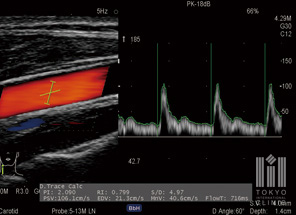

頚動脈超音波検査

仰向けに寝た状態で首にゼリーを塗り、動脈硬化を診断します

CAVI検査

心臓や頚動脈が脳梗塞にも関連することから、心電図や頚動脈超音波検査も実施。複合的に脳の状態を調べます